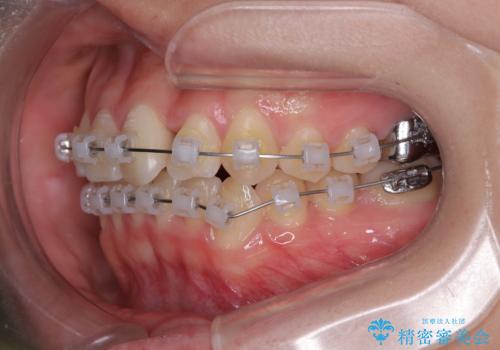

治療方法としては、装置の目立ちにくさと費用面のバランスを考慮して、プラスチック製のクリアブラケットとメタルワイヤーを組み合わせた矯正装置を使用することにしました。

また、上顎前歯の重なっていた部分にはむし歯が見つかり、治療中に適切な処置を行っています。